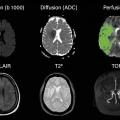

L’imagerie par résonance magnétique (IRM) est l’examen le plus approprié (figure). Elle doit comporter quatre séquences :2

• la séquence de diffusion, qui identifie les lésions ischémiques récentes sous forme d’un signal hyper­intense en b 1000 et d’une diminution du coefficient apparent de diffusion de l’eau. Ces changements sont très précoces, contrairement à ceux observés en séquence FLAIR (fluid-attenuated inversion recovery) ;

• la séquence T2* écho de gradient ou de susceptibilité (SWI), qui permet de repérer très précocement les hémorragies. Elle est donc cruciale pour différencier ischémie et hémorragie, et pour identifier la présence de microsaignements chroniques (microbleeds) ;

• la séquence FLAIR, qui identifie les lésions anciennes d’origine vasculaire ou d’autre nature. Dans l’ischémie cérébrale, elle ne révèle la présence d’un infarctus qu’après un délai de quatre à six heures. Elle est utilisée comme une horloge tissulaire permettant d’évaluer une heure de début inconnue ou de préciser une heure de début approximative donnée par l’entourage ;

• la séquence ToF (time of flight), qui visualise le polygone de Willis et identifie les occlusions d’artères intracrâniennes.

La séquence de perfusion peut être utile pour visualiser la zone de pénombre ischémique, mais elle n’est pas utilisée en routine car elle allonge la durée de l’examen dans un contexte d’urgence. Elle n’est réellement utile que chez les patients vus plus de quatre heures trente après l’apparition des symptômes, ou pour les diagnostics différentiels de type trouble neurologique fonctionnel ou migraine avec aura.